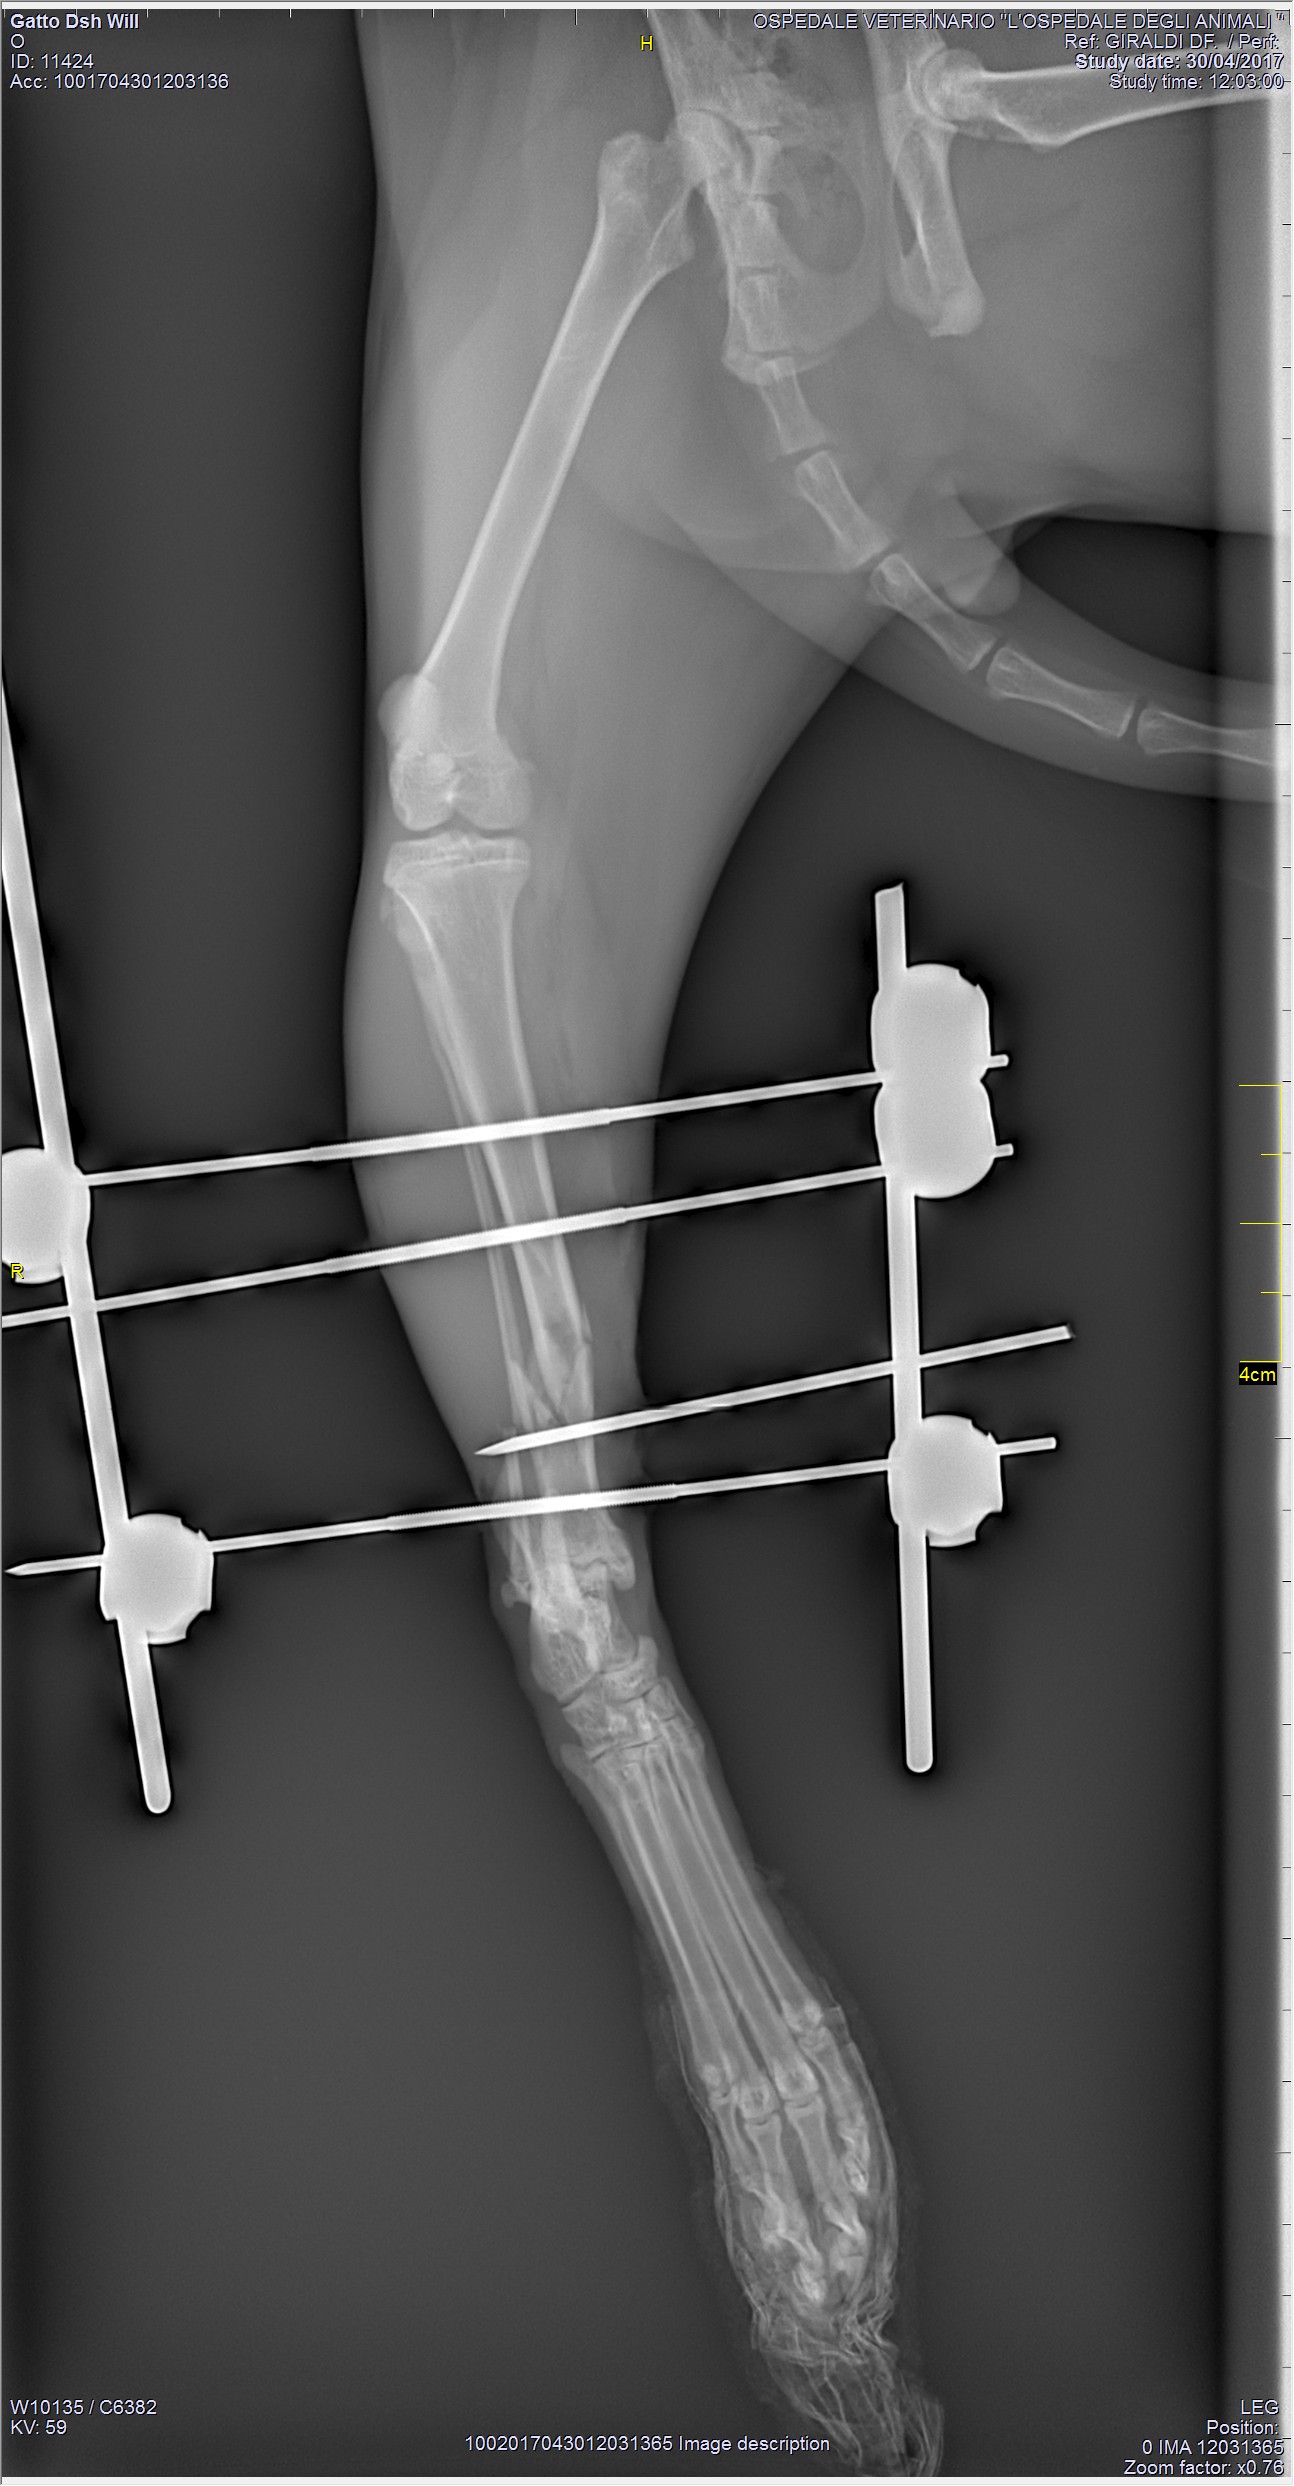

TTA - Tibial Tuberosity Advancement

La TTA (Avanzamento della Tuberosità Tibiale) è una tecnica relativamente nuova per il trattamento della rottura del legamento crociato craniale. La tecnica è stata fortemente influenzata da considerazioni biomeccaniche ed ha, come la TPLO, lo scopo di annullare le forze che agiscono sul legamento crociato craniale del ginocchio tramite un riassetto della conformazione dello stesso.

La tecnica è meno invasiva delle procedure alternative, minimizza i tempi chirurgici e preserva il range of motion articolare. Il recupero dal punto di vista clinico è più rapido rispetto alle altre tecniche.

La TTA si inserisce nel panorama mondiale come una tecnica in grado di modificare la geometria del ginocchio per trattare la rottura del legamento crociato craniale, quindi si pone come obiettivo non quello di ricostruire il legamento lesionato ma bensì quello di modificare la biomeccanica del ginocchio.